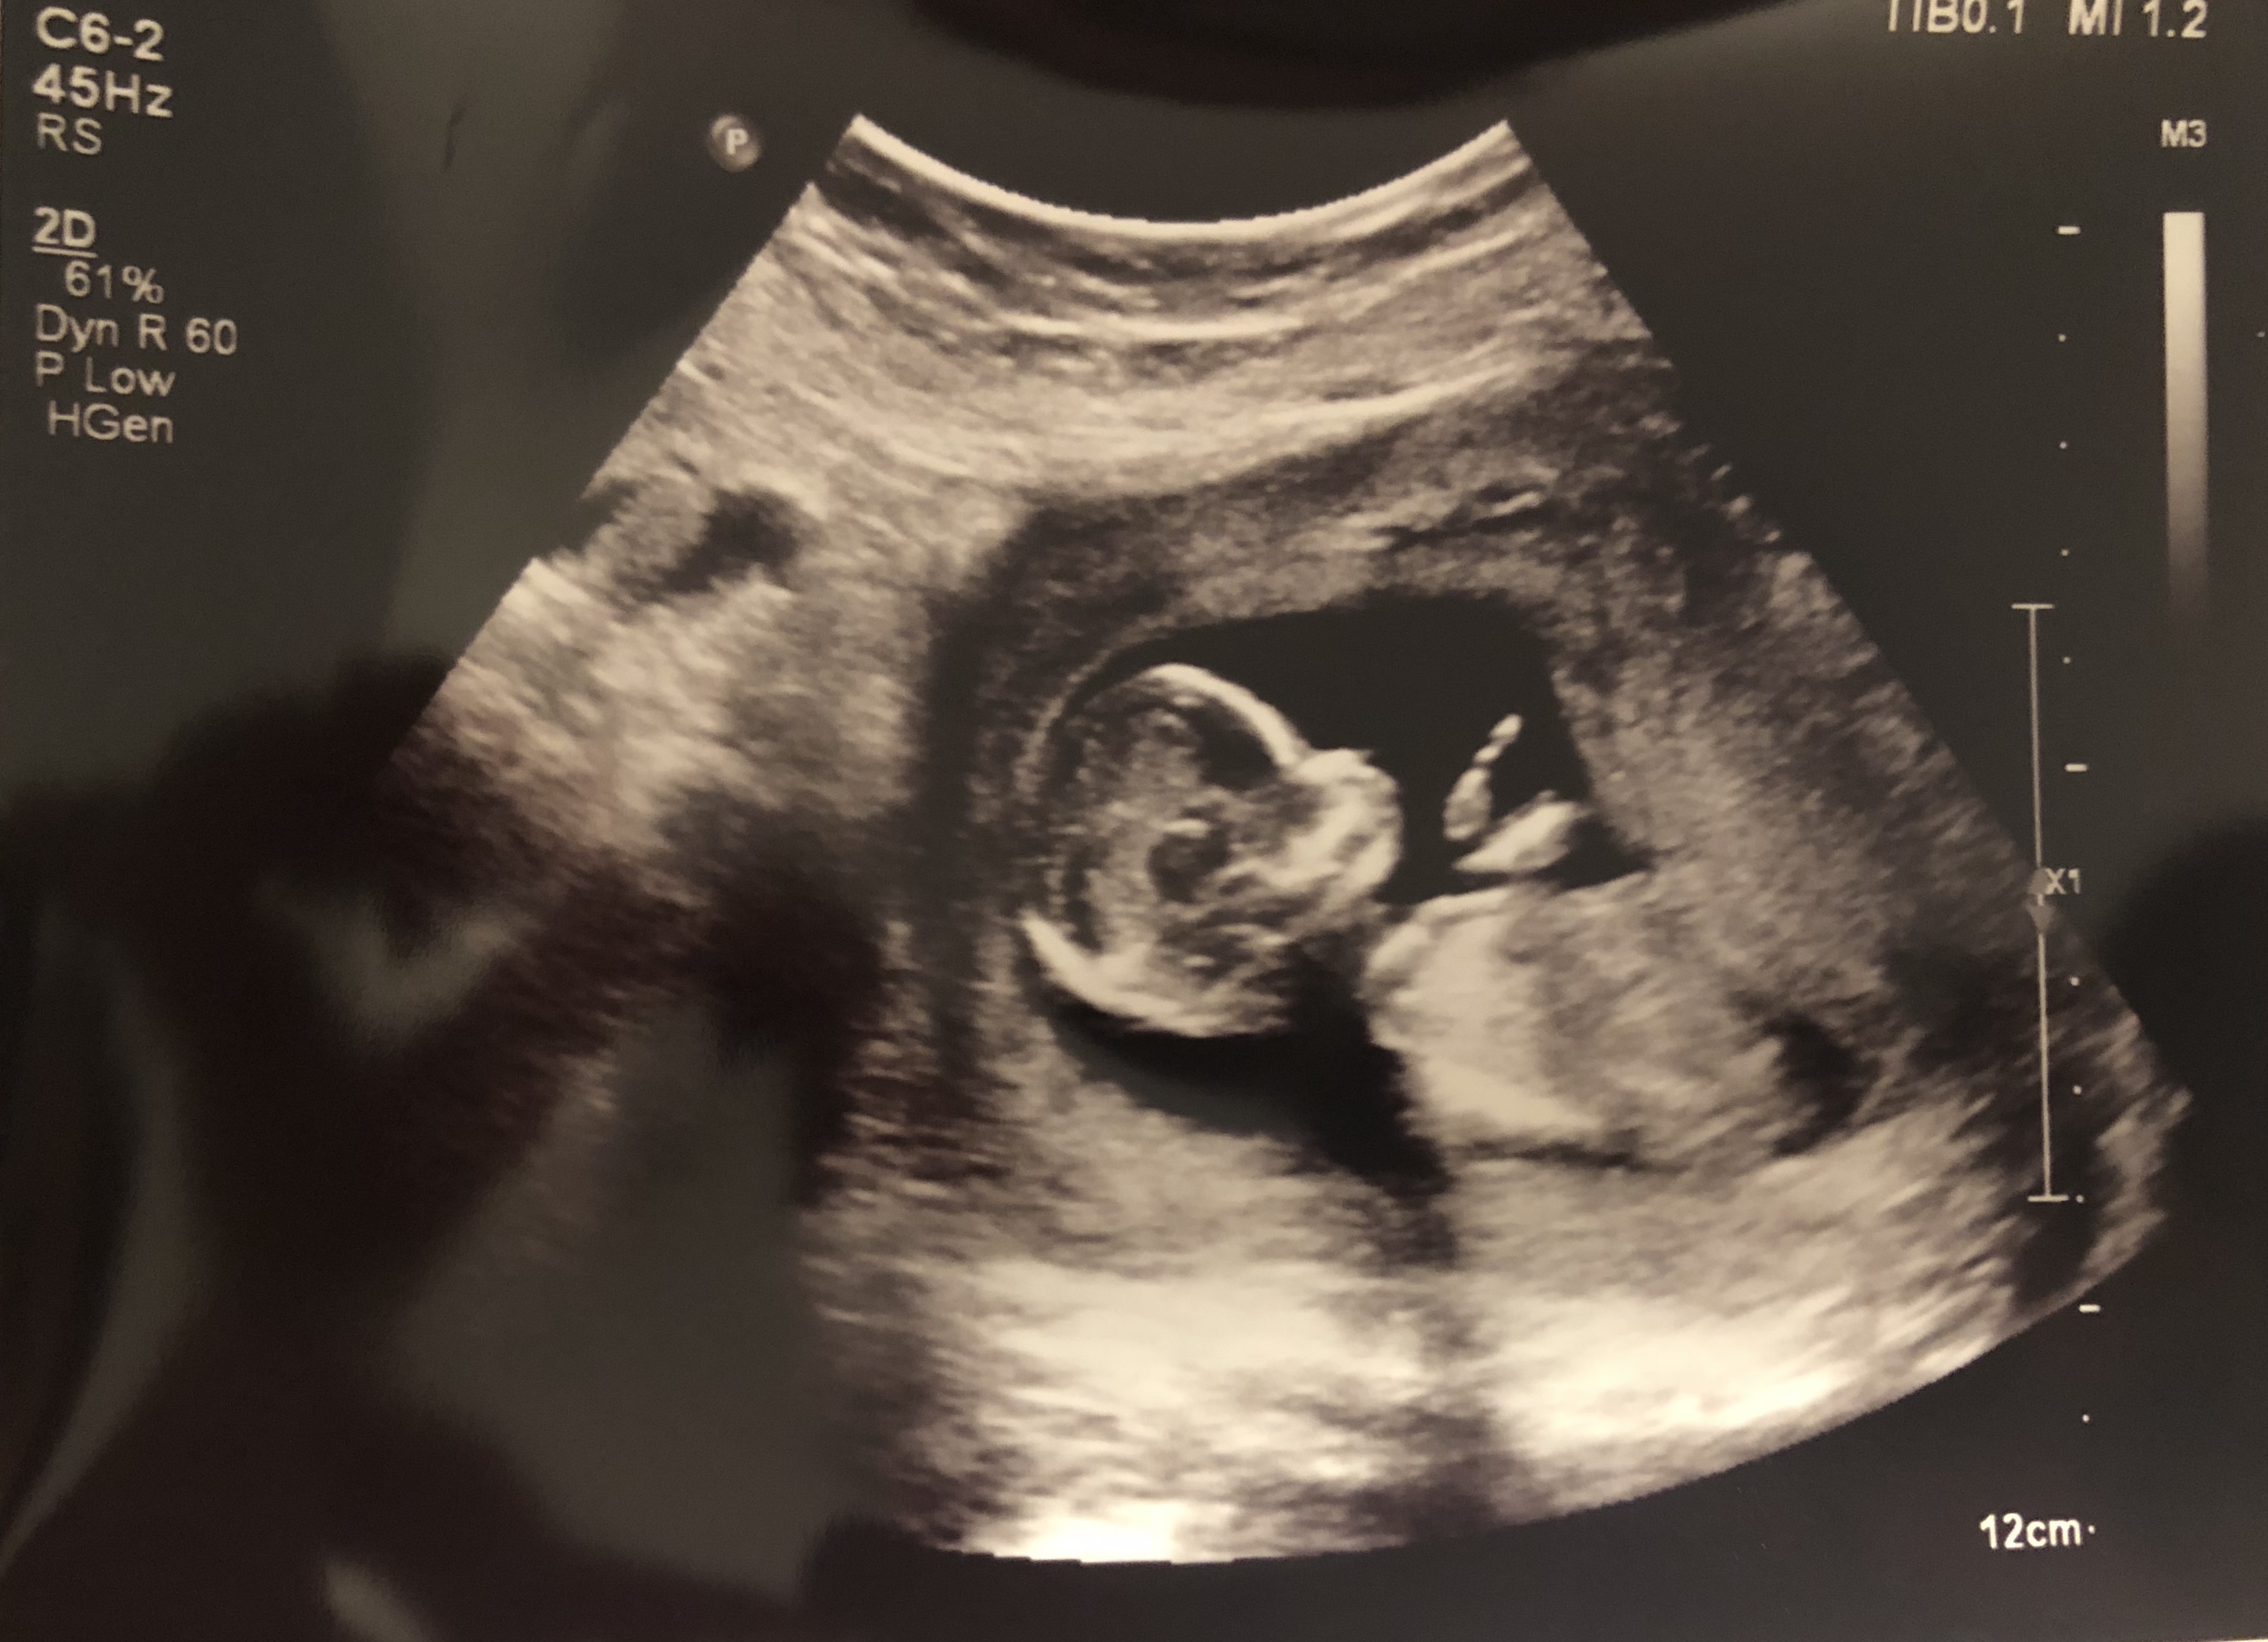

Can anyone guess my baby gender by skull theory?

14w

Attachment 40781